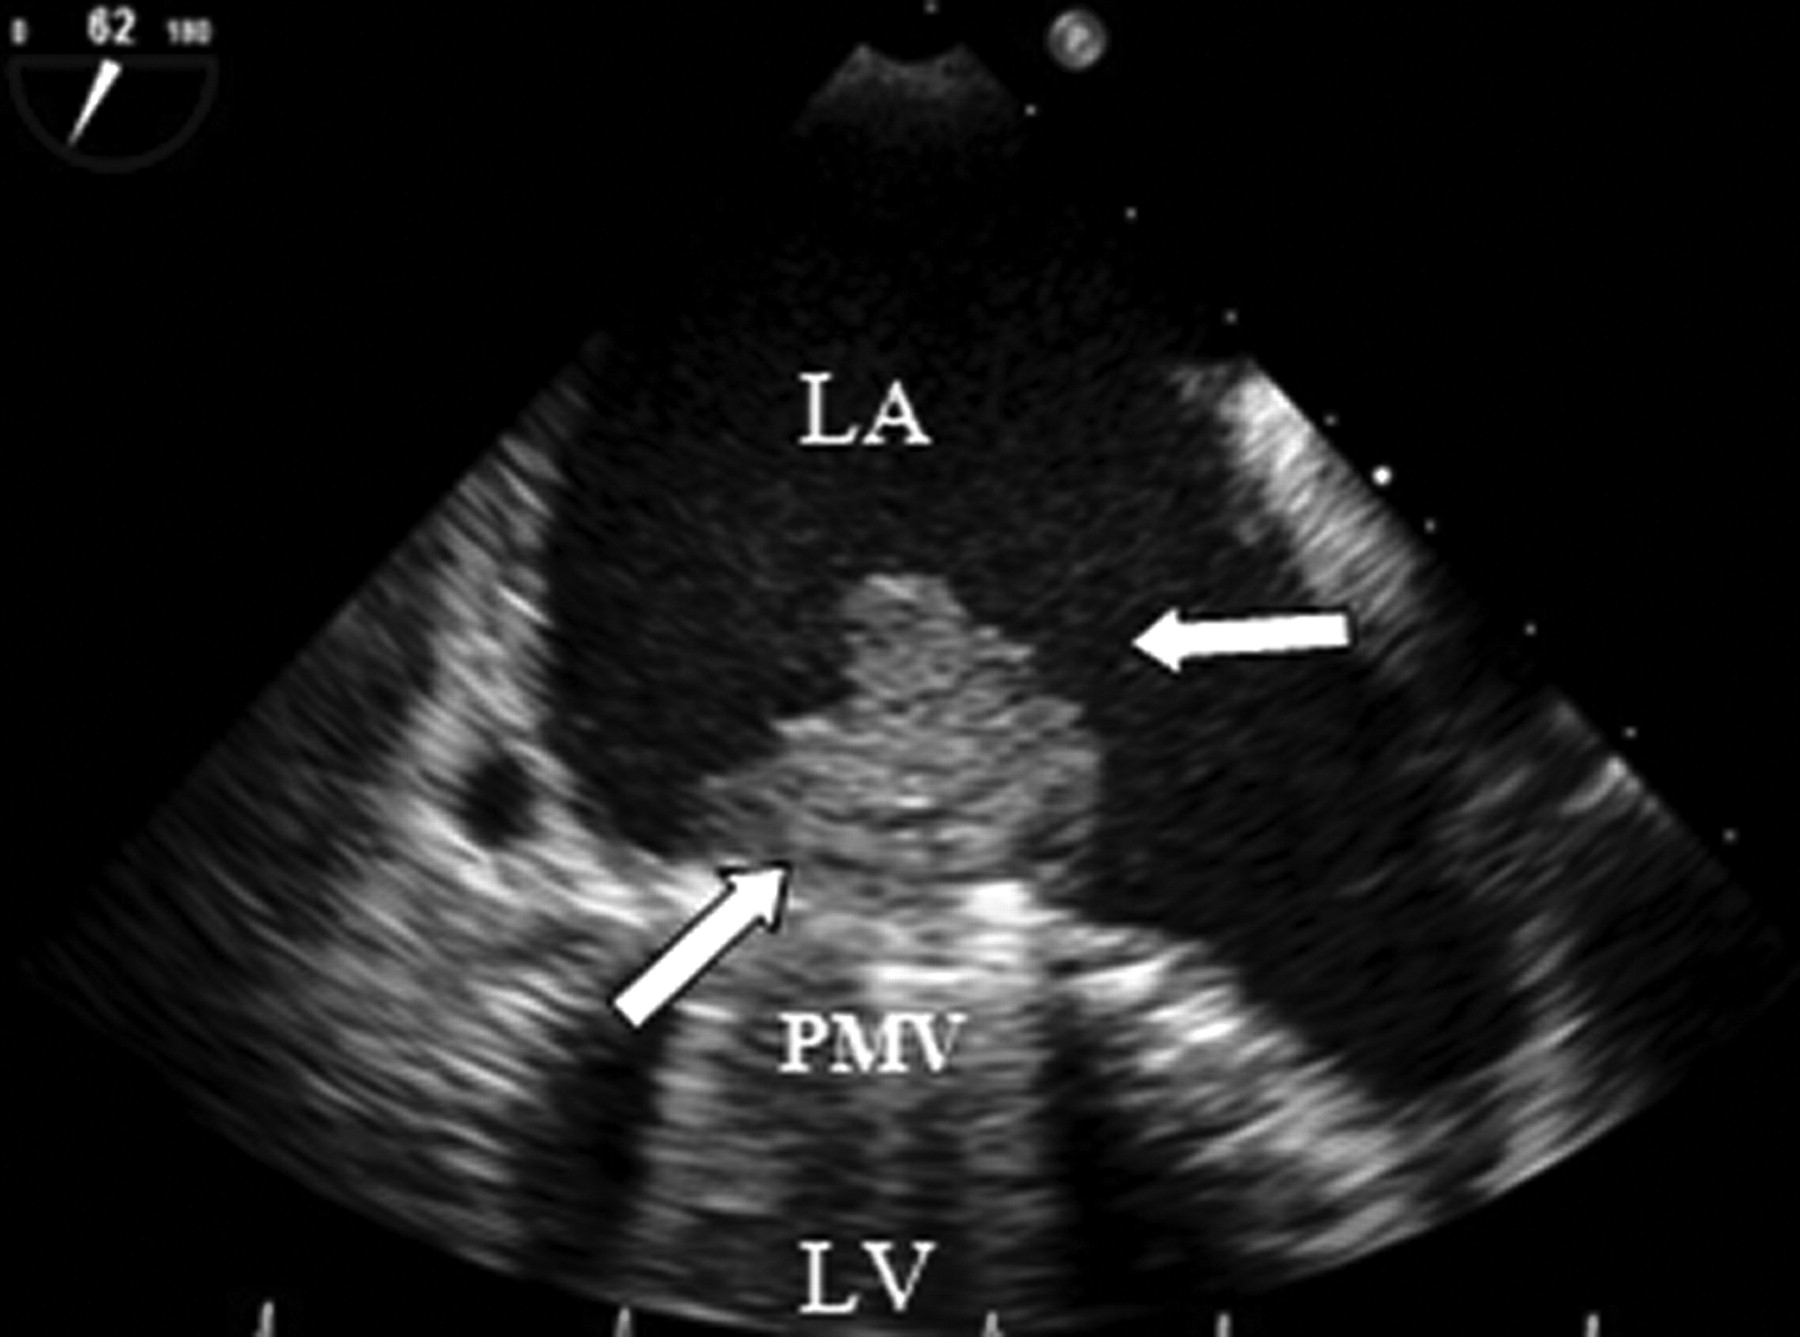

Estenose Mitral e Parâmetros Discordantes: